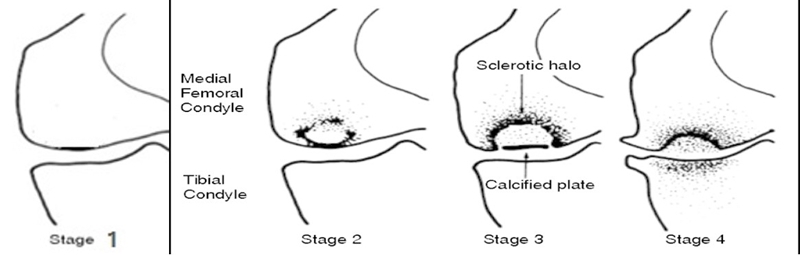

目前SONK诊断最常用的分期方法是1979年Koshino提出的分期法。Koshino分期基于临床和影像学的结果,将SONK分为四个阶段:

Ⅰ期:患者有膝关节症状,但影像学正常;

Ⅱ期:X线显示负重区变平,软骨下信号升高,周围有骨硬化;

Ⅲ期:受影响区域扩大和软骨下塌陷;

Ⅳ期:病变周围骨硬化和髁突周围骨赘形成的退行性阶段。

1979年Koshino分期